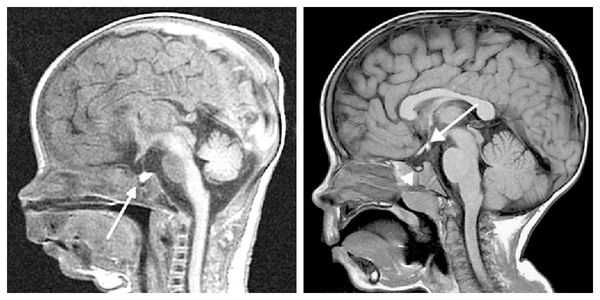

При необходимости проводится МРТ головного мозга и гипофиза с контрастированием [6] . Она позволяет исключить или подтвердить наличие объёмных образований области гипофиза и головного мозга.